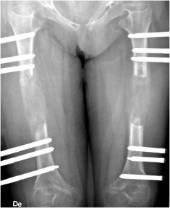

Dependiendo de la talla del paciente se realizará un alargamiento bilateral de femur o alargamiento bilateral de tibia.

ALARGAMIENTO BILATERAL DE FÉMUR

El fémur es un hueso especial debido a su forma, tamaño (el hueso más grande del cuerpo) y por estar envuelto en una gran masa muscular por lo que las fuerzas distractoras que se oponen al alargamiento son muy potentes.

Por otro lado en la cara interna del muslo están los vasos y nervios que van a la extremidad y limita la colocación de fijadores externos en esta zona, es por lo que los clavos intramedulares están ganando indicaciones.